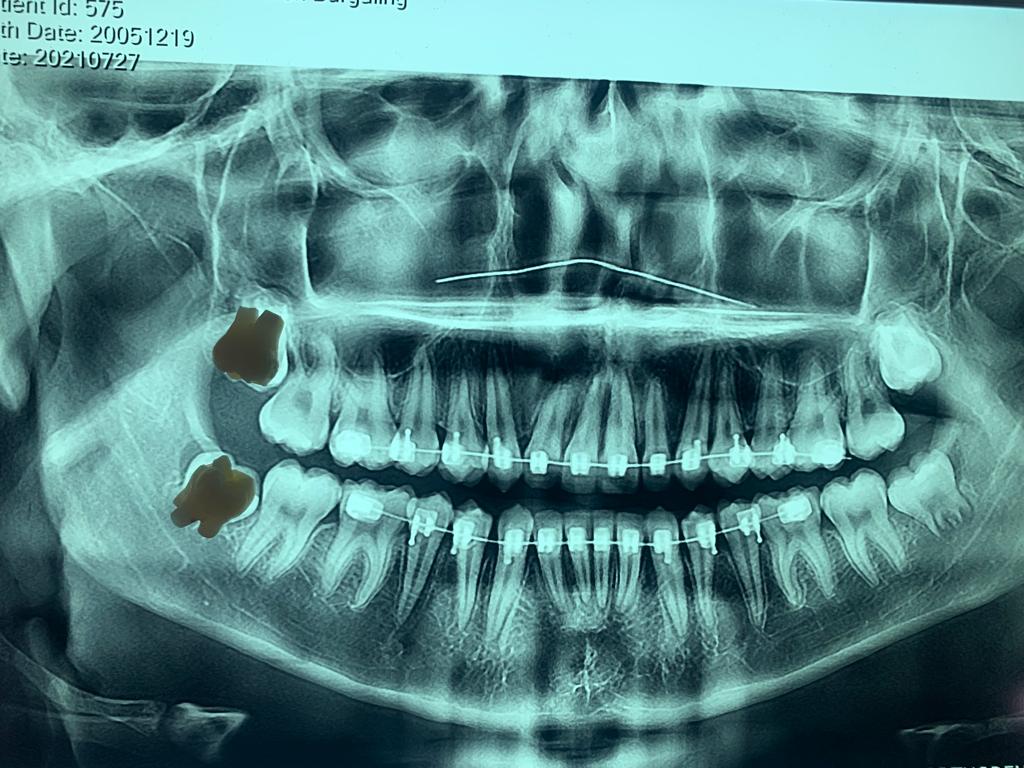

Galería

ortodoncia

Es una especialidad de la odontología que se encarga de la corrección de los dientes posicionados incorrectamente.